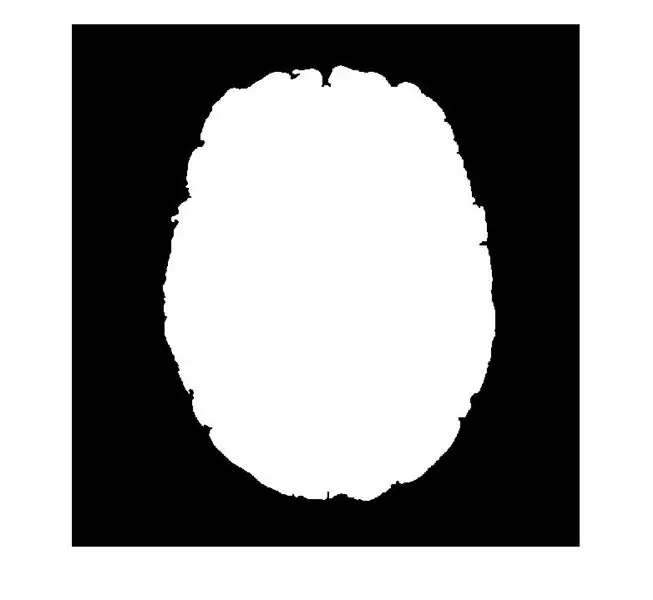

Чтобы правильно обработать ваше изображение, вы хотите сначала преобразовать его в двоичное изображение. Бинарное изображение - это просто изображение, состоящее из единиц и нулей, соответствующих черным или белым пикселям. Для вашего изображения мы собираемся установить пороговое значение для нашего изображения, чтобы оно принимало значения пикселей, превышающие установленный порог (возможно, вам придется немного поиграть с числом. Может быть, начните со 150) и преобразует их в единицы. Таким образом, мы можем немедленно избавиться от любых участков изображения, которые слишком темны, чтобы быть опухолью.

В Matlab мы можем сделать это, введя код:

I = imread ('имя_файла_образа');

фигура 2); thresha = I> 150 и I <260;

imagesc (thresha); палитра (серый);

Это отобразит двоичное изображение, которое удаляет слишком тусклые или слишком яркие пиксели, в этом случае значения пикселей от 150 до 260 будут установлены на 1, а другие значения - на 0.